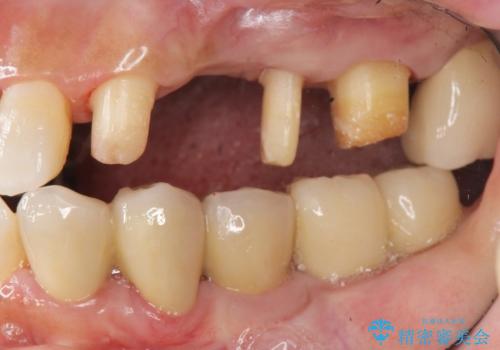

- 全体的に歯が揺れ、このままでは全て歯を失うのではないかと怖くなり歯周病治療を希望され来院されました。

歯列不正による第一小臼歯の骨吸収が認められ、機能咬合力の回復、大きな側方力に連結することで抵抗することのできるブリッジ補綴を選択しました。

歯周病による深いポケット・大きな側方力・短い臨床歯根・欠損の補綴、これらの問題を解決するために歯周補綴を兼ねたブリッジを選択しました。